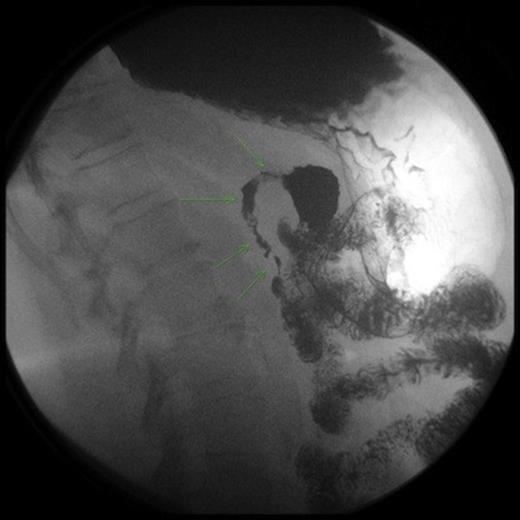

An upper endoscopy showed distal tertiary esophageal contractions, small sliding hiatal hernia with mild gastroesophageal reflux, and an intestinal obstruction at the level of the second portion of the duodenum. The mucosa was normal with the lumen completely constricted. A CT scan demonstrated distension of the stomach and first portion of the duodenum. An UGI study showed severe stenosis of the second portion of the duodenum.